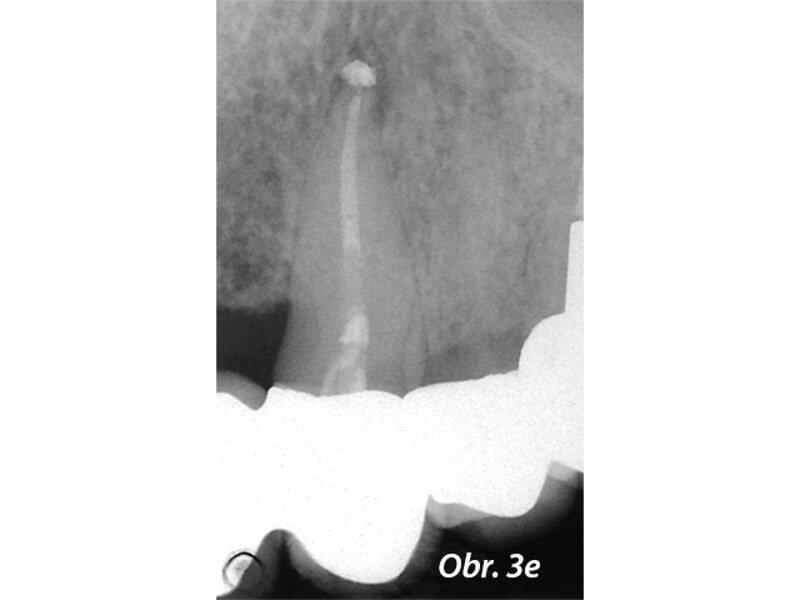

Aplikace MTA s použitím Produit Dentaires (PD) MAP System